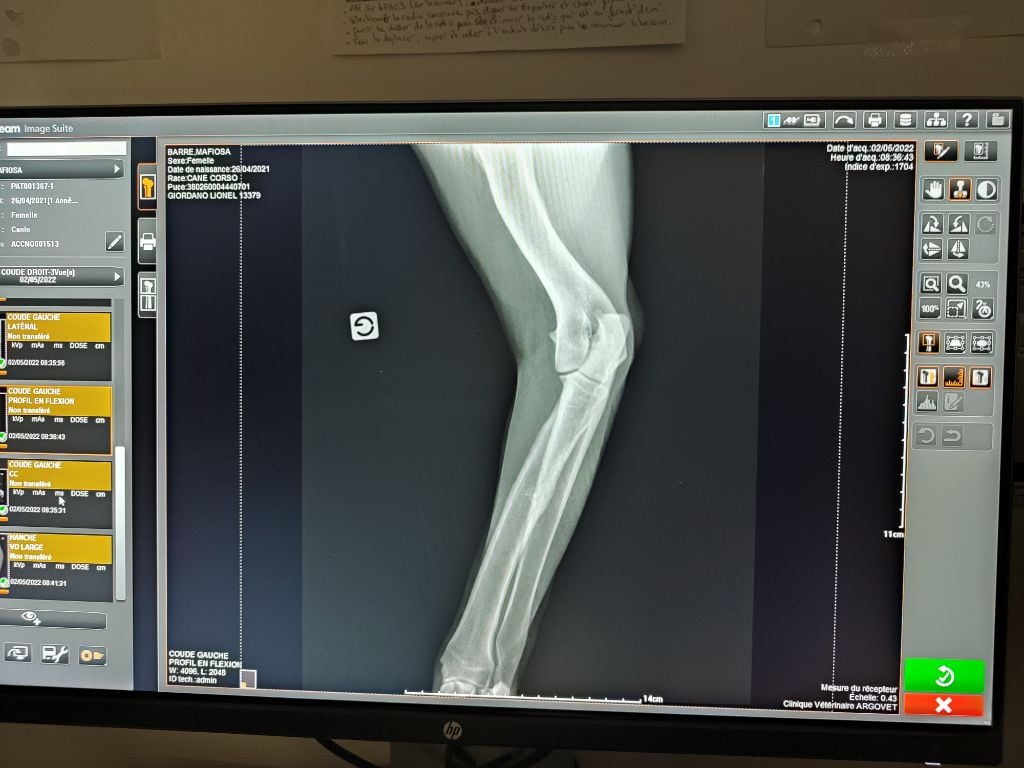

Cane Corso

| Sexe | Femelle |

| Couleur | noire ADN HD C / ED 0/ DSRA N/N |

| Puce | 380260004440701 |